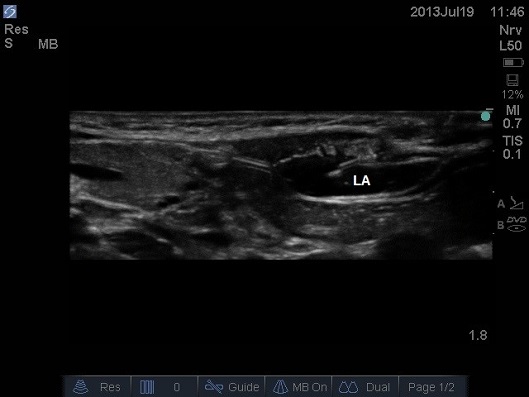

ULTRASOUND OF NEONATAL ABDOMEN IN THRANSVERSE PLANE. THE LOCAL ANAESTHETIC (LA) PEELS THE POSTERIOR SHEATH OFF THE RECTUS MUSCLE.

- A ‘pop’ is not always present and it may be necessary to repeat the test injection of local anaesthetic.

- In neonates prevent waste of precious local anaesthetic by using saline to detect the correct plane.

- Deposit local anaesthetic in the potential space between the rectus abdominis muscle and the posterior aspect of the sheath.